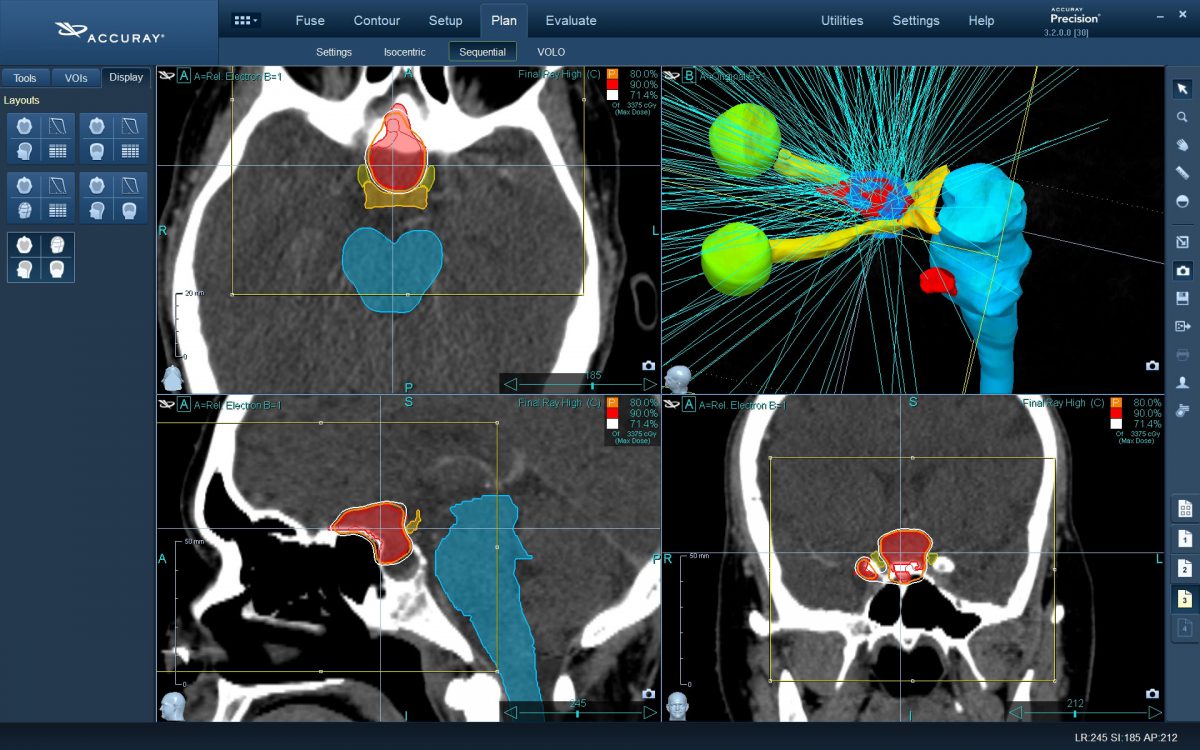

Ο νευροχειρουργός Λέκας Λεωνίδας έχει τη μεγαλύτερη εμπειρία στην Ελλάδα στο σχεδιασμό θεραπειών στερεοτακτικής ακτινοχειρουργικής όγκων του εγκεφάλου και του νευρικού συστήματος σε CyberKnife. Ο σχεδιασμός του πλάνου θεραπείας προϋποθέτει άριστη γνώση της ανατομίας και της απεικόνισης του κεντρικού νευρικού συστήματος έτσι ώστε να επιτευχθεί το βέλτιστο θεραπευτικό αποτέλεσμα με τη μέγιστη δυνατή προστασία των ευαίσθητων δομών.

Η θεραπεία παραδίδεται από έναν μικρού βάρους γραμμικό επιταχυντή (LINAC), προσαρμοσμένο σε ένα εξελιγμένο ρομποτικό βραχίονα (Kuka robotics). Ο τελευταίος επιτρέπει την εκτέλεση κινήσεων με 6 βαθμούς ελευθερίας (6-DOF). Αυτό σε συνδυασμό με τεχνολογία αιχμής στην στόχευση βλάβης σε πραγματικό χρόνο (real time image guided targeting system), επιτρέπει την εκτέλεση εξαιρετικά δύσκολων θεραπειών με εκατοντάδες διαφορετικές λεπτές δέσμες ακτίνων X με ακρίβεια δεκάτων του χιλιοστού (submillimeter accuracy).

Φυσικά και όχι. Το CyberKnife M6 της Accuray Inc. USA είναι το πιο εξελιγμένο σύστημα ρομποτικής ακτινοχειρουργικής στον κόσμο, όμως δεν παύει να είναι ένα σύστημα που υπακούει πάντα στις ανθρώπινες εντολές. Ο σχεδιασμός και το πλάνο της θεραπείας εκπονείται πάντα από ομάδα ιατρών και ακτινοφυσικών με την χρήση των πιο εξελιγμένων συστημάτων λογισμικού ακτινοθεραπείας (Accuray Precision Treatment Planning). Το ρομπότ τελικά θα εκτελέσει με ακρίβεια δέκατου του χιλιοστού το πλάνο θεραπείας που του παραδόθηκε.